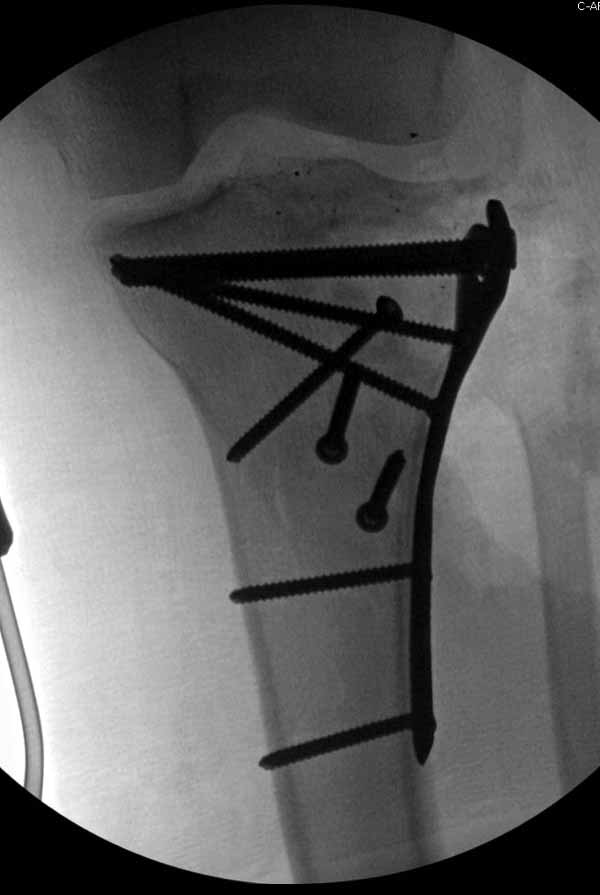

Больная Л., 23 года. Из анамнеза:со слов больной в 2006 г. появились боли правой н/конечности, обратилась поместу жительства к хирургу, было выполнена МРТ поясничного отдела позвоночника,назначено физиолечение. Через 2 месяца боли прекратились, через 4 месяца рецидив болевого синдрома. С 2006 – 2010 проводилось консервативное лечение по поводу остеохондроза поясничного отдела позвоночника. В октябре 2010 г. боли усилились. Выполнены Ro и КТ правого тазобедренного сустава, выявлен очаг патологической перестройки. Была направлена на консультацию в УНИИТО. В УНИИТО виюне 2011 г. поставлен дифференциальный диагноз между фибромой, солитарной костнойкистой и гигантоклеточной опухолью.

Клиника и течение заболевания похожи на однокамерную кисту. Больная молодая, желательно сохранить собственную головку. Надо спешить с операцией, иначе скоро произойдет перелом через тонкую стенку. Во время операции внутри будет пустота и небольшое количество жидкой крови.

Из всех перечисленных методов подходит вариант пластики аутокостью и усиление (арматура) шурупами. Основная задача сохранить интактную медиальную стенку и латеральный кортекс. Доступ передне-латеральный, но надо работать спереди шейки через небольшое окно в 10-15 мм. Фиксацию надо проводить между медиальной тонкой стенкой головки и латеральным кортексом. Каннюлированные шурупы 6.5 мм очень грубые и могут разрушить остаток стенки. Фиксировать надо кортикальными шурупами 3.5 мм, которые создадут мостик и арматуру в шейке. Провести по периметру шейки 4, и в центре пару шурупов. Во время операции и при манипуляции соблюдать осторожность, в любой момент может наступить стресс перелом. Заранее надо заказывать длинные шурупы!